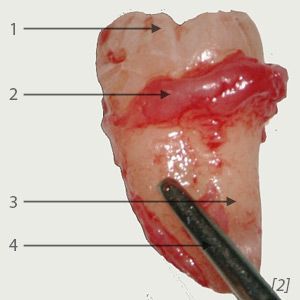

Bild 2: extrahierter Weisheitszahn

1 – Zahnkrone;

2 – Reste des Zahnsäckchens;

3 – Zahnwurzel;

4 – Pinzette